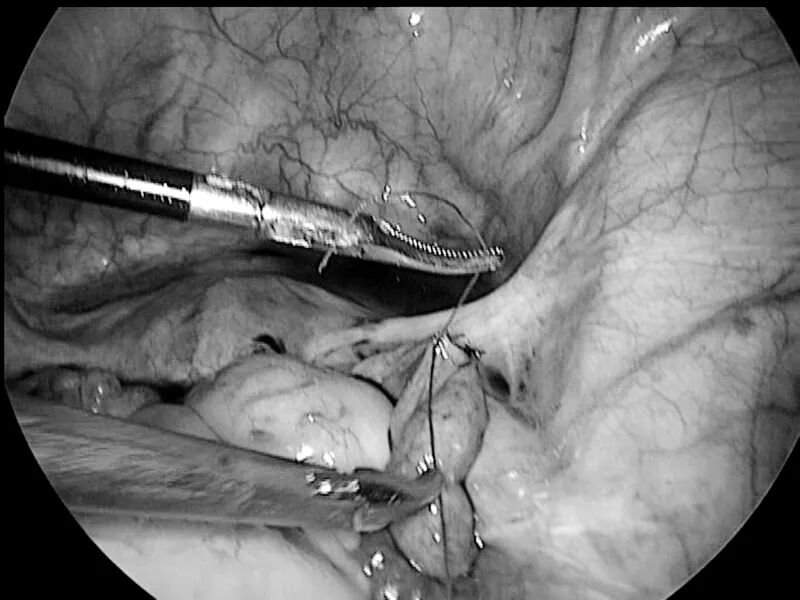

“这个手术主要是在腹腔镜下将原来结扎的输卵管切开,并剪除以前结扎的伤疤,再重新将两侧断开的输卵管用线缝合好。”在周留林的口中,这个说起来简单的手术,但做起来却并不容易。

输卵管是连接在子宫两侧的管状结构,长度在8—14cm之间。管腔直径最大处也不超过1cm,最窄处在0.9—2mm,将如此细微的输卵管缝合难度可见一斑。“缝合时需要特别注意对合要良好,稍有偏差就会使输卵管扭曲或者会影响其管腔的通畅度,这样都会影响术后患者的怀孕成功率。这考验手术医生的技术和经验,是目前较难的妇科手术之一。”

当天,经过近两小时的精细操作,周留林团队为其实施了腹腔镜下输卵管再通手术。手术最后,当腹腔镜下见到双侧输卵管均顺畅地流出了输卵管通液后,手术室内的同事都纷纷喝彩。